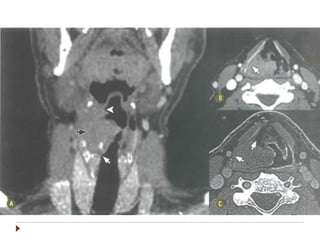

 Disseminação para linfonodos dos

níveis II, III, IV, V e retrofaríngeos.

Orofaringe  Mais agressivoque CEC de nasofaringe, com pior prognóstico.  Disseminação para linfonodos dos níveis II, III, IV, V e retrofaríngeos.  Sintomas: odinofagia, halitose, sangramento, perda de peso, linfonodo palpável.

• 24.

• 25.

• 26.